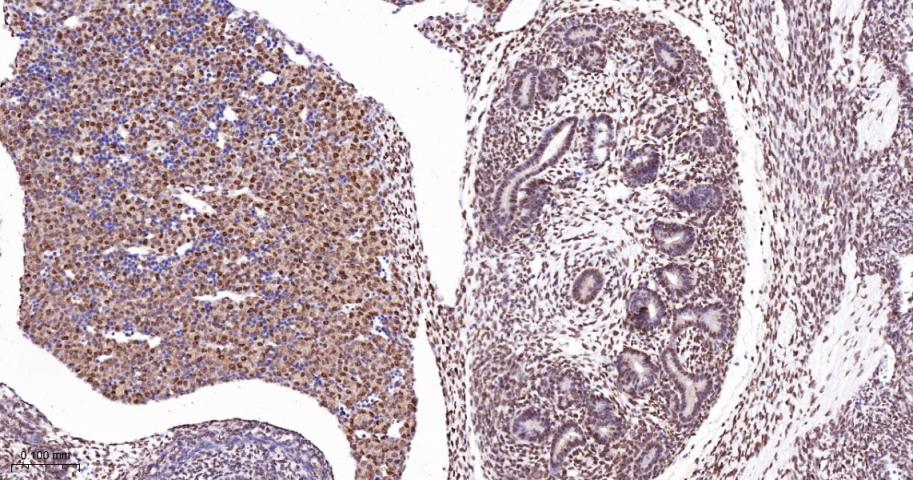

Paraformaldehyde-fixed, paraffin embedded Human Ovarian mucinous carcinoma; Antigen retrieval by boiling in sodium citrate buffer (pH6.0) for 15 min; The section was incubated with PTBP1 Monoclonal Antibody, Unconjugated (bsm-60550R) at 1:200 overnight at 4°C, followed by conjugation to the bs-0295G-HRP and DAB (C-0010) staining.

Paraformaldehyde-fixed, paraffin embedded Human Colon Cancer; Antigen retrieval by boiling in sodium citrate buffer (pH6.0) for 15 min; The section was incubated with PTBP1 Monoclonal Antibody, Unconjugated (bsm-60550R) at 1:200 overnight at 4°C, followed by conjugation to the bs-0295G-HRP and DAB (C-0010) staining.

Paraformaldehyde-fixed, paraffin embedded Human Small Intestine; Antigen retrieval by boiling in sodium citrate buffer (pH6.0) for 15 min; The section was incubated with PTBP1 Monoclonal Antibody, Unconjugated (bsm-60550R) at 1:200 overnight at 4°C, followed by conjugation to the bs-0295G-HRP and DAB (C-0010) staining.

Paraformaldehyde-fixed, paraffin embedded Human Spleen; Antigen retrieval by boiling in sodium citrate buffer (pH6.0) for 15 min; The section was incubated with PTBP1 Monoclonal Antibody, Unconjugated (bsm-60550R) at 1:200 overnight at 4°C, followed by conjugation to the bs-0295G-HRP and DAB (C-0010) staining.